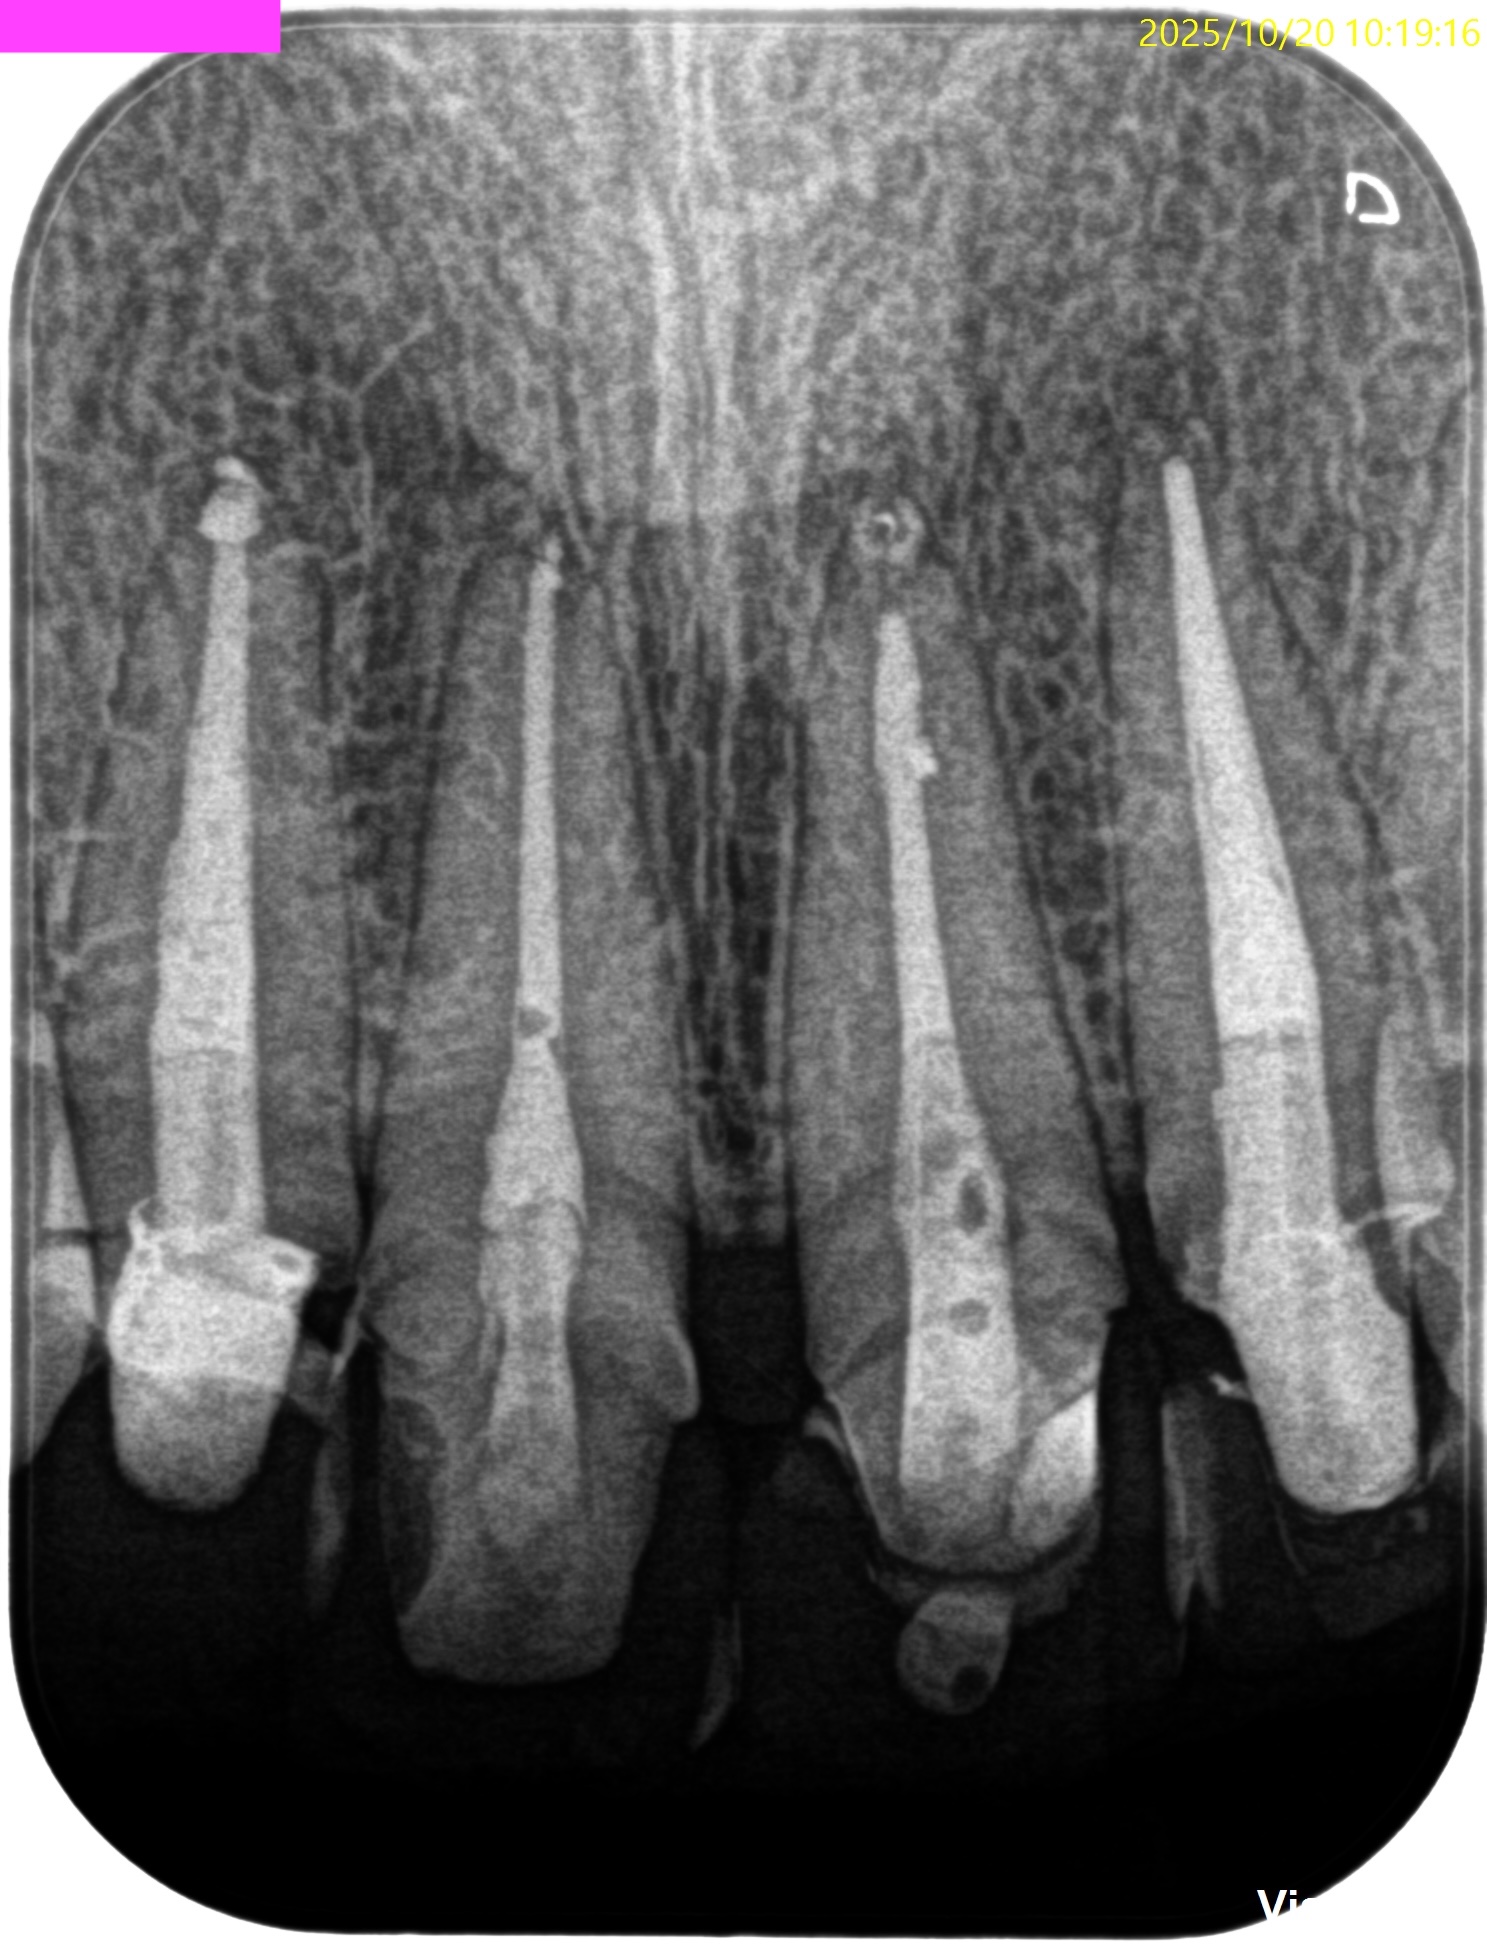

#7,10 Re-RCT 10M recall(2025.10.20)

症状が消失している。

ということは、治癒しているのだろうか?

が、この絵だけで治癒しているかどうか?判断がつくだろうか?

無理だ。。。

そこで、CBCTも撮影した。

#7

#10

これでも判然としかねる。

そこで、

CareStream(日本ではヨシダ社)のCBCTなら以下のようにMPR(Multi-Planar Reconstruction)画面を作成することができる。

それを過去のそれと比較してみた。

↓

このMPR画像からこの患者さんは#7,10ともに外科治療など要らないということがわかるだろう。

無論、検査の結果からそれは必要はないと言えるが、

客観的に不要であるということを患者さんに伝えるにもこの画像機能(MPR画像)は非常に有効である。

ということで今日は、このMPR画像機能について論じてみた。